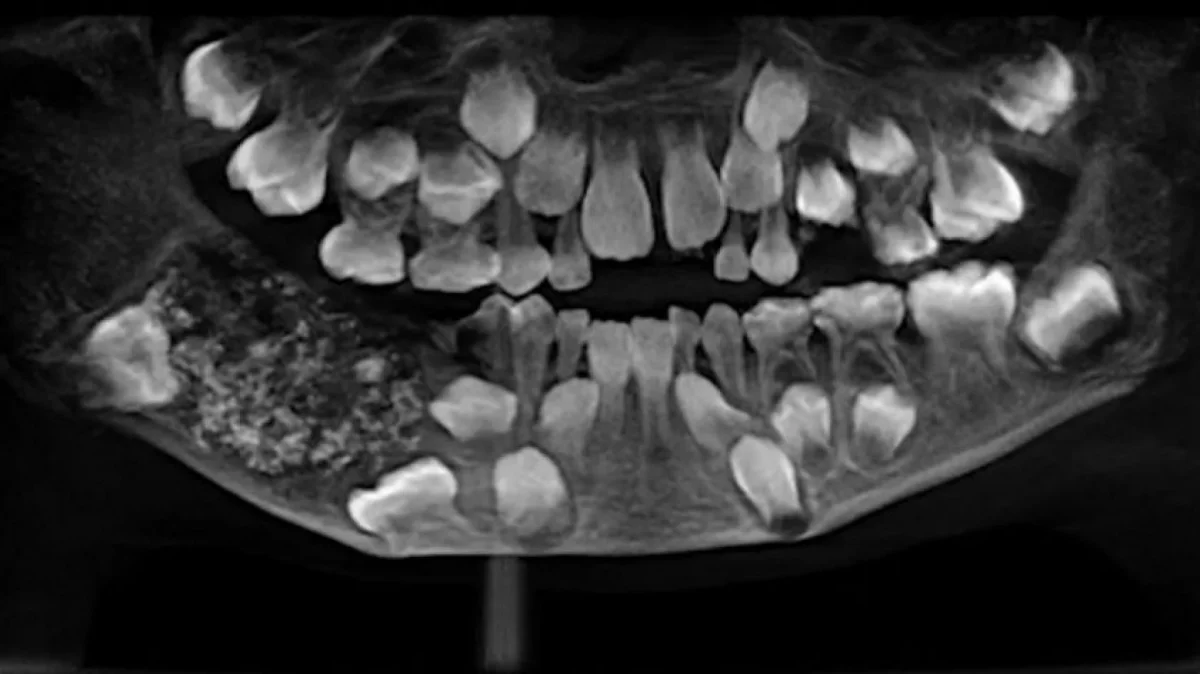

El menor desarrolló una extraña condición llamada odontoma en el lado derecho de la mandíbula. La operación duró más de cinco horas y, si bien fue exitosa, a futuro el paciente deberá usar prótesis especiales. El nene, de nombre Ravindranath, había desarrollado una patología en la parte derecha de la mandíbula desde los tres años y le causaba grandes molestias.